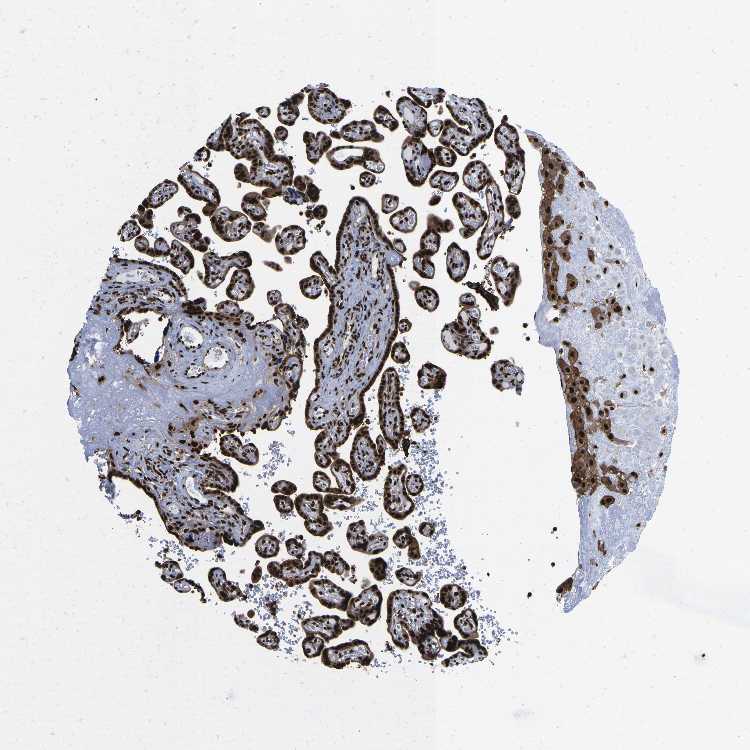

PLACENTA